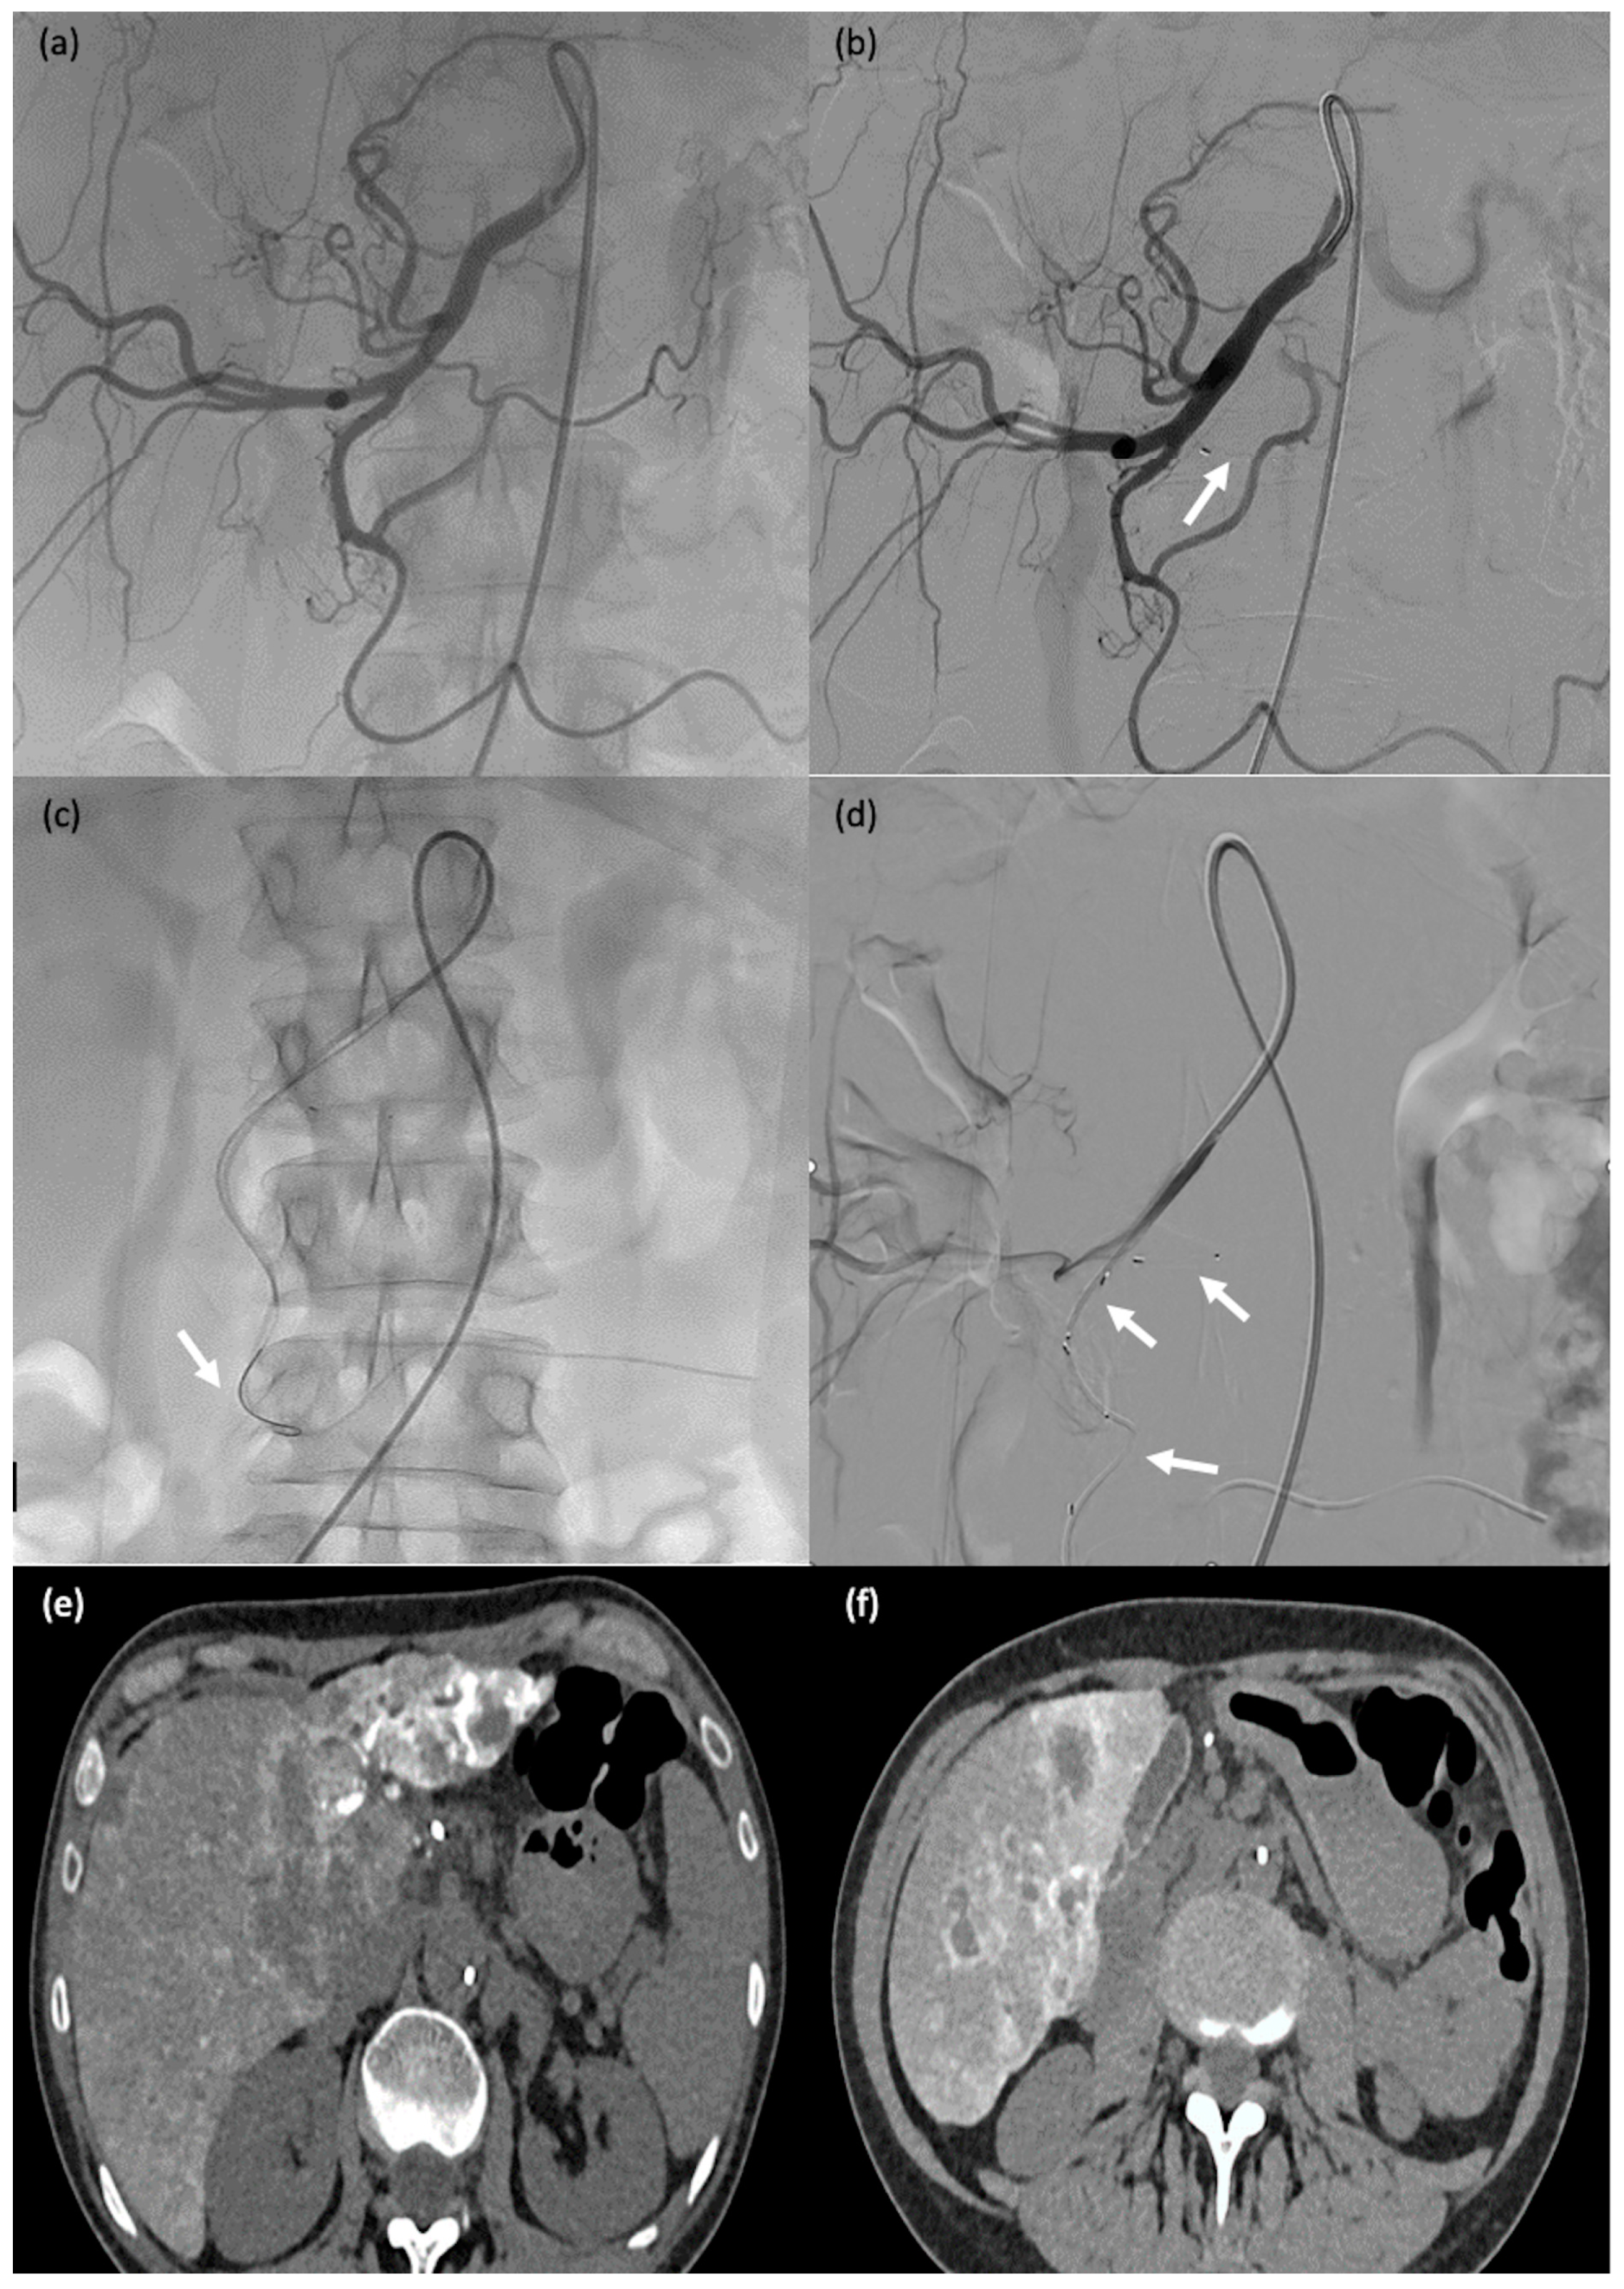

Figure 3. A 60-year-old man (#1) with diffuse metastatic disease from colonic cancer that was unresponsive to chemotherapy and required intensification via chemotherapy port catheter implantation. (a,b) MVP-3Q implantation (arrow) to occlude the left gastric artery before insertion of the chemotherapy catheter. (c,d) Catheter insertion in the gastroduodenal artery, occlusion of the gastroduodenal artery and stabilisation of the chemotherapy catheter via implantation of 2 MVP-3Qs through a smaller microcatheter inserted in the side-whole of the chemotherapy catheter (arrows). (e,f) Computed tomography after arterial contrast medium administration showing excellent enhancement of all metastatic lesions in both liver lobes.